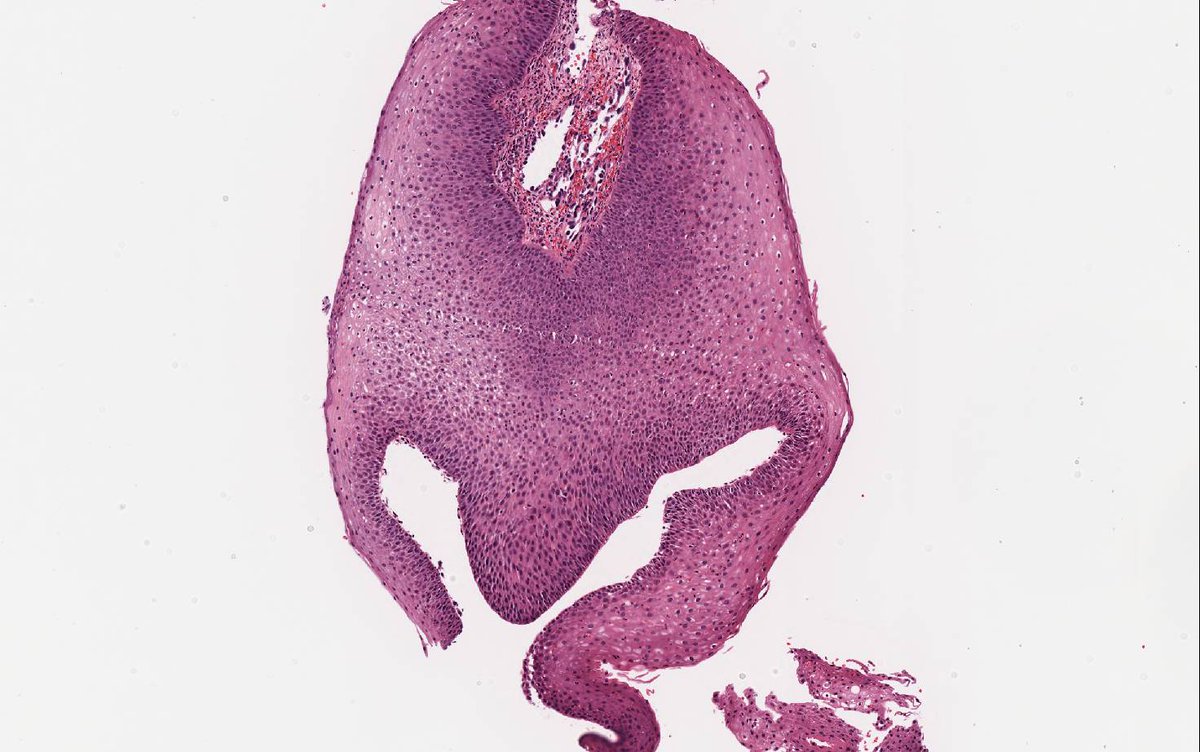

Remember leiomyosarcomas arising from vessels may be aggressive unlike leiomyosarcoma from arrector pili. This LMS arising from vein; note residual vascular wall at periphery. Residual vein top left corner on image 2 & 3. Ref: Italiano A, et al. PubMed PMID: 20167595. #dermpath